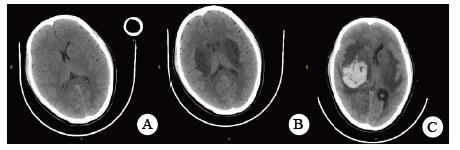

当晚20时到达本院,入院时患者昏迷,血压低、心肌损伤、轻度心衰, 低氧血症, 肝损伤。相关实验室检查:血气PaO2 44 mmHg,生化指标谷丙转氨酶(ALT)528.8 U/L,谷草转氨酶(AST)780.9 U/L,胆红素正常,尿素氮(BUN)3.6 mmol/L,肌酐(Cr)125.7 μmol/L,血糖7.88 mmol/L,心肌肌酐蛋白(cTnT)55.94 ng/mL,N末端B型利钠肽原(NT-pro BNP)495.7 pg/mL,神经元特异性烯醇化酶(NSE)47.46 ng/mL。胸部CT未见明显异常(图 1),头颅CT未见明显异常(图 2A)。给予异甘草酸镁保肝,乙酰半胱氨酸抗氧化,兰索拉唑保护胃黏膜,并予血液灌流治疗一次。

| A:入抢救室当日(中毒首日);B:住院第5天(中毒第6天);C:住院第8天(中毒第9天) 图 2 患者头颅CT影像 |

次日晚间收住入院。住院第2天监测血压99/72 mmHg。实验室检查:cTnT 245.4 ng/L,NT-pro BNP 18.57 pg/mL,BUN 2.68 mmol/L,Cr 40.5 μmol/L,血钾3.82 mmol/L。血气:PO2 116 mmHg,pH 7.498, Lac 1.58 mmol/L。并CRRT治疗:治疗前APTT为32.2 s,阿加曲班抗凝,治疗剂量40 mL/(kg·h)。第3天继续CRRT治疗,阿加曲班抗凝,监测APTT为62.9 s(为正常值2倍)。第4天停CRRT, 记录自发尿量1 920 mL /24 h。第5天神志逐步转清,有指令动作,自主呼吸良好,停机械通气。脱机拔管后查颅脑CT双侧基底节区及脑干低密度影, 考虑中毒性脑病改变(图 2B),胸部CT未见明显异常。监测APTT为26.7 s。第7天患者再次昏迷,并有呼吸急促,脉氧下降。再次行气管插管呼吸机支持。监测肝功能进一步好转(ALT 187.7 U/L,AST 92.2 U/L)。第8天17时发现患者瞳孔不等大,左侧3.5 mm,右侧4.5 mm, 对光反射消失,即查颅脑CT示右侧基底节区出血(图 2C)。家属要求保守治疗。第9天患者处于深昏迷状态,家属放弃继续治疗出院。出院一周后随访患者死亡。

哒螨灵口服中毒后机体细胞内呼吸功能抑制,导致细胞缺氧,无糖酵解,乳酸快速堆积,机体迅速出现代谢性酸中毒,重要脏器灌注不足,早期即可表现肝功能异常甚至肝衰竭;心肌酶谱增高,心肌收缩力减低,胰腺功能受损,血淀粉酶增高,血糖应激性增高[3]。由于人体脑组织供应的血流非常丰富,因此对缺氧表现也非常敏感。但哒螨灵中毒并发脑病报道较少,并发脑出血者罕见。该例患者中毒后出现恶心呕吐,提示该药对胃肠道有刺激性;后出现多系统损伤。早期即出现意识障碍,并渐加重至昏迷,有脑神经元损伤,但早期头颅CT未见明显异常;患者有严重低血压,需要大剂量血管活性药物维持血压;患者严重低氧血症,需要呼吸机支持,但肺部影像学未见明显异常;患者有乳酸酸中毒、肝肾功能损伤和心肌受损,但上述损伤大多在支持治疗2~4 d后完全正常或出现明显好转。但第5天头颅CT提示患者出现中毒性脑病表现,患者神志在短暂好转后又再次恶化,第8天原右侧基底节区水肿部位出现脑出血。